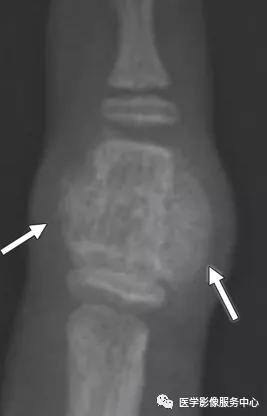

桡侧副韧带撕脱损伤:

(左)撕脱骨片略示移位(白色箭头),累及桡侧副韧带在第一近端指骨桡侧基底部的连接处。(右)桡侧副韧带从其指骨连接处的部分层厚撕裂(白色箭头),不伴有撕脱骨折。注意尺侧副韧带损伤也存在(白色长箭头)